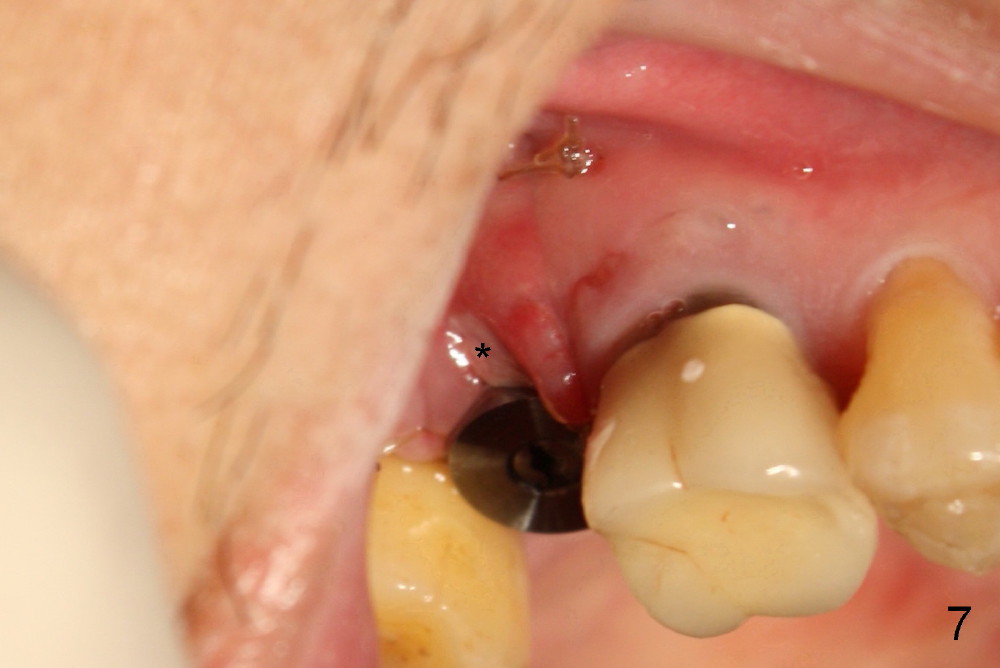

The implant threads (T) are exposed buccally. A flap is raised (Fig.5) with periosteum underscored. After placement of Osteogen (HA 300-500 µm) and Collaform (a collagen membrane, Fig.6*), the flap is sutured. There is no intra- or post-op nasal hemorrhage. The wound heals (Fig.7 (5 days postop), 8 (18 days)). It is apparent that the membrane (Fig.7 *) is replaced by the healing gingiva (Fig.8 *). Three months postop, the buccal gingiva looks normal (Fig.9) around the stable implant (Fig.10).